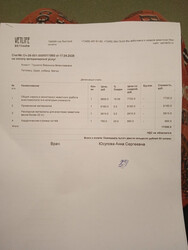

24 апреля мы поехали домой! В смысле в приют, который Шура считает своим домом, пока другого ей никто непредложил. Счёт за дни в Юне с 21 по 24 апреля на сумму 8163,83 ниже

Наконец то свели все цифры по затратам на операцию для Шурочки:

РАСХОД:

-Ветлайф 52965

-лекарства 8116

-Юна 27168,81

————————

Всего 88 249,81₽

СПАСИБО ОГОРОМНОЕ всем, кто помогает.    Вся сумма, потраченная на операцию Шуре, собрана, долги закрыты! Вся сумма, потраченная на операцию Шуре, собрана, долги закрыты!